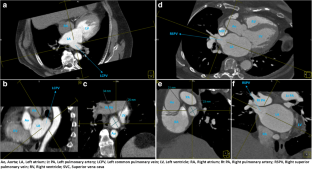

Fig. 1

Fig. 2